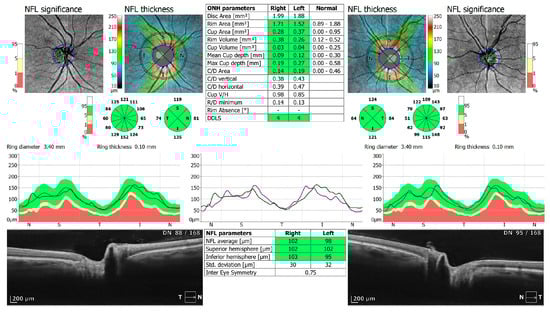

Figure 3.

OCT 3D disc scan 6 × 6 mm of COVID-19-positive patient. NFL, nerve fiber layer; ONH, optic nerve head.